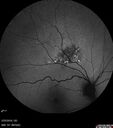

Amelanotic Nevus - OCT findings

60 year old man with normal vision. Nevus is 1 mm tall and was stable over 6 years follow-up

Amelanotic Choroidal Nevus352 views60 year old man. Nevus is stable over 6 years. Images are Photo, FAF, OCT, FA, ICG, and B-Scan     (0 votes)